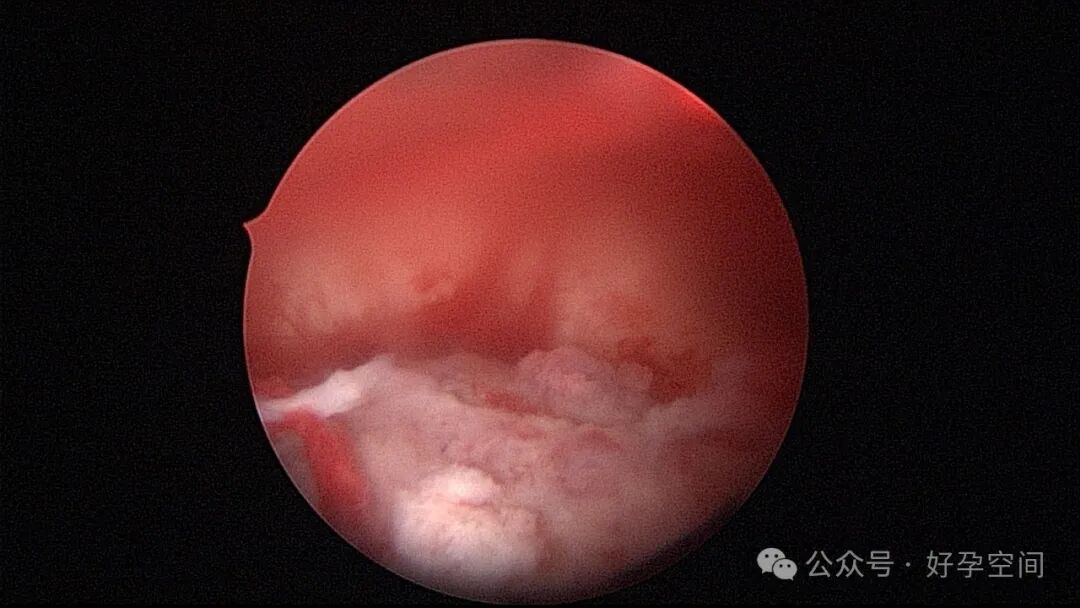

病例1:32岁,G8P3,剖宫产3次,本次停经50+天,计划外妊娠,宫腔镜辅助下清宫,见剖宫产瘢痕憩室,宫腔后壁2.5cm*2.0cm组织难以清除,宫腔镜电切送病检,病检结果为宫腔妊娠组织。

病例2:32岁,G3P1,剖宫产1次,本次停经60+天,稽留流产,宫腔镜辅助下清宫,宫腔广泛粘连,单极电针分粘。术后19天宫腔镜二探,宫腔后壁见1.0cm*1.0cm组织凸起,宫腔镜电切送病检,病检结果为宫腔增殖期样子宫内膜,另见血凝块及纤维素样坏死组织,浅肌层内可见少许滋养叶细胞(病理医生曾与临床医生沟通,病理图片跟超常胎盘部位反应很相似,但最后仅给出了以上病检诊断)。